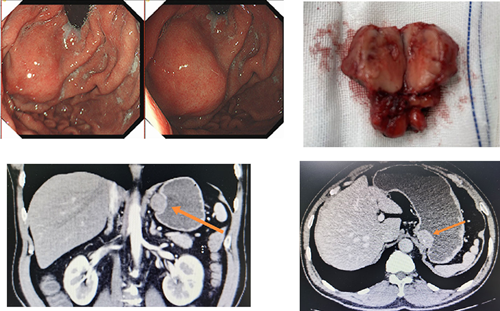

a(左上),b(中上),c(右上)和d(左下)显示胃经下行胃内黏膜下肿瘤剜除术

【原创】双镜联合切除胃体肿瘤